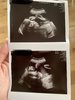

Nooo to ciotki 😇 jestem po usg :) z Rozalką wszystko Ok, będzie modelka 😂 długie nóżki ma i o dziwo waga bardzo dobra 😂 Ok 1,2 kg

A pępowina 2 naczyniowa jest.. ale mała sobie najwidoczniej nic z tego nie robi ✊🏻 Twarda jest 🤓

Usg trwało chyba z 3 min 😂 ale najważniejsze, że z dzieciątkiem wszystko dobrze 🥰

• 382390A4-0A1F-47A3-9C7C-74AC98A34EF0.jpeg